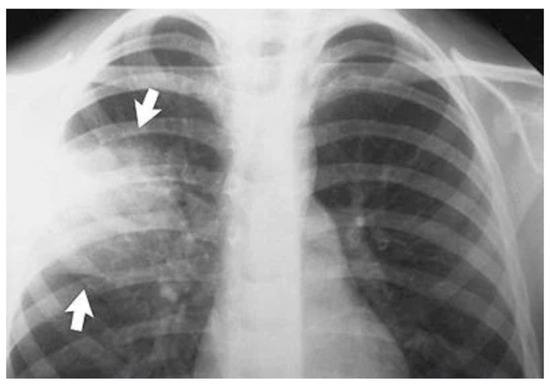

1.1. Pneumonia Imaging Modalities

- Variability in Image Quality: Chest X-ray image quality can vary significantly, making it challenging to identify subtle abnormalities.

- Overlapping Features: Pneumonia patterns may overlap with other lung conditions, leading to misinterpretations.

- Subjectivity: Interpretation of X-rays is subjective and relies on radiologist expertise.

- Size and Location of Infection: The size and location of pneumonia can affect its visibility in X-rays.

- Co-occurring Conditions: Patients with pneumonia may have co-occurring conditions that complicate interpretation.

- Children and Elderly Patients: Detecting pneumonia in children and the elderly can be challenging due to anatomical and age-related differences.

- Evolution of Infections: Pneumonia can evolve rapidly, and X-ray findings may change.

- Atypical Presentations: Pneumonia may present atypically, deviating from typical radiographic patterns.

- Data Imbalance: Imbalanced datasets can lead to biases in model performance.